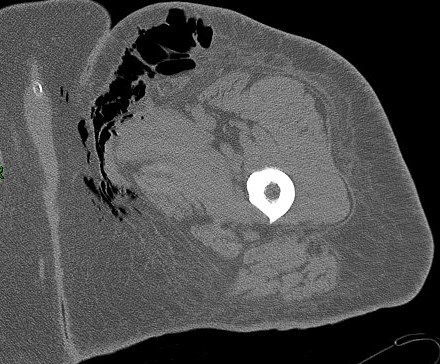

46 yoF history of small abscess in upper thigh which worsened quickly.

The soft tissue air is essentially pathognomic. Reference article.

Necrotizing fasciitis ( RID3447 )